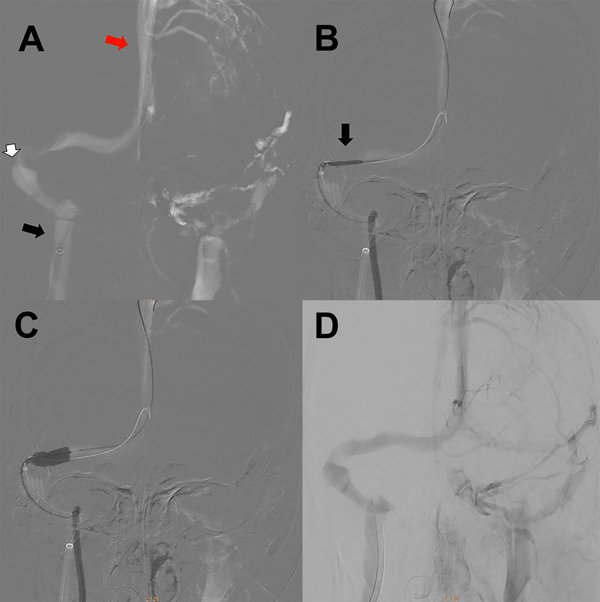

A la paciente se le había ofrecido cirugía de colocación de una válvula de derivación pero la misma rechazó esa opción. Se le realizó una angioRM con tiempos venosos que evidenció la presencia de estenosis de seno transverso derecho (figura 1) por lo que fue derivada a nuestro centro. Le realizamos una angiografía cerebral por punción radial derecha objetivando una estenosis del seno transverso derecho (figura 2A). A la vez, le realizamos un cateterismo venoso por punción femoral derecha y monitoreamos la presión a ambos lados de la estenosis del seno transverso (figura 2B). La presurometría evidenció un gradiente de presión entre el seno longitudinal superior y el seno sigmoideo derecho de 15mm de Hg (figura 2C) por lo que decidimos realizar la angioplastía del seno transverso a nivel de la estenosis.

Figura 2: A) Angiografía cerebral digital con adquisición frente en tiempo venoso. La flecha negra señala la estenosis del seno transverso derecho. B) Detalle de la venografía digital en la unión de los senos transveros y sigmoideo. Se detalla la medición del seno transverso en los segmentos estenosado y no estenosados. La flecha negra señala el catéter de acceso distal localizado en la porción proximal a la estenosis. C) Imagen del monitor durante la medición de tensión venosa en todo el trayecto del seno transverso. La flecha blanca marca la medición a nivel proximal a la estenosis (presión media 20mm de Hg). La flecha amarilla marca la medición a nivel distal a la estenosis (presión media 5mm de Hg). El gradiente de presión a través de la estenosis es de 15mm de Hg.

Le indicamos clopidogrel 75mg/día y AAS 100mg/día desde una semana antes del procedimiento. Bajo anestesia general le realizamos un abordaje arterial radial derecho y un abordaje venoso femoral derecho con introductor 5Fr. Se anticoaguló con 10.000 UI de heparina. Bajo guía 0.035 se realizó el recambio del introductor femoral por una vaina carotídea 6Fr progresando la misma hasta el golfo de la yugular derecha. Bajo una guía hidrofílica 0.035 ascendimos un catéter de acceso distal 6Fr hasta el seno sigmoideo derecho (figura 3A). Luego realizamos la angiografía cerebral para determinar el segmento venoso estenosado. Sobre una guía 0.014 localizada en el seno longitudinal superior, bajo roadmap navegamos con técnica rapid exchange un stent balón expandible de cromo-cobalto de 7 por 18mm (Herculink, Abbot) (figura 3B). Una vez localizado el stent a nivel de la estenosis insuflamos el balón con 11 atmósferas hasta llevar el segmento estenosado a diámetros similares a los adyacentes al mismo (figura 3C y 3D). Luego de implantado el stent, realizamos la presurometría del segmento angioplastiado evidenciando un gradiente de presión de 2mm de Hg. Se realizaron todos los controles angiográficos y se retiraron los catéteres arterial y venoso, también se realizó TC de cerebro sin evidencia de complicaciones (figura 4).

Figura 3: A) Imagen angiográfica en modo roadmap incidencia antero-posterior en tiempo venoso. La flecha negra muestra el extremo distal de la vaina carotídea a nivel del golfo de la vena yugular. La flecha blanca indica el extremo distal del catéter de acceso distal en el seno sigmoideo. La flecha roja muestra el extremo distal de la microguía 0.014 a nivel del seno longitudinal superior. B) Imagen angiográfica en modo roadmap incidencia antero-posterior en tiempo venoso. La flecha negra muestra el stent balón localizado en la posición de la estenosis previo a la impactación del mismo. C) Imagen angiográfica en modo roadmap incidencia antero-posterior en tiempo venoso. El balón ya fue inflado en el sitio de la estenosis. D) Angiografía cerebral digital con adquisición frente en tiempo venoso luego de la impactación del stent en el seno transverso derecho sin estenosis residual.